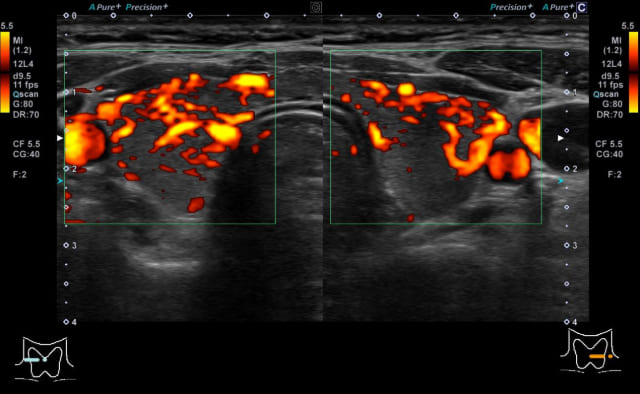

抗甲状腺薬の注意する副作用に無顆粒球症があります。無顆粒球症は300~400人に1人起こるとされ、細菌に対する免疫力低下を起こすので、扁桃炎発症が疑うきっかけになります。扁桃の腫れと発熱を起こした場合には、白血球減少がないか採血をする必要があります。無顆粒球症は服用開始(再開)後3か月以内に多いため、開始後2ヶ月は2週間毎に血液検査をする必要があります。当院では甲状腺ホルモン過剰の症状が強い方には、当日に甲状腺ホルモン、甲状腺関連抗体検査、甲状腺エコーを実施し、バセドウ病の診断がついた方には当日に治療を開始していますので、症状でお困りの方はご相談ください。

本症はバセドウ病と比べると、FT3/FT4比やFT4値が低かったり、TSH受容体抗体が陰性または低値のことが多く、甲状腺エコーで上甲状腺動脈の最高流速速度も低い、などの特徴があります。本症と診断された場合は、一般的にはバセドウ病のくすりは服用せずに経過観察をします。甲状腺ホルモンが過剰の時期から低下症の時期を経ますが、多くは2か月程度で正常に戻ります。低下症になってすぐには、低下症が継続するかの判断は難しく(抗甲状腺関連抗体陽性例では低下症継続の率が上がることは参考になります)、この時期で開始した補充療法は途中で中止できる可能性があります。

甲状腺超音波(エコー)検査では、甲状腺は基本的には全体的に大きくなり、内部は粗くみえることが多いです。臨床診断は、甲状腺の全体的な腫大に加えて、TgAbまたはTPOAb陽性で行います。甲状腺機能が正常であれば治療の必要はありません。機能が低下している場合には飲み薬(チラーヂンS®、レボチロキシン®)によって甲状腺ホルモンの補充を行います。服用は一日一回です。(吸収の安定性からは空腹時の服用がよく、また金属系製剤と同時服用は避ける必要があります)